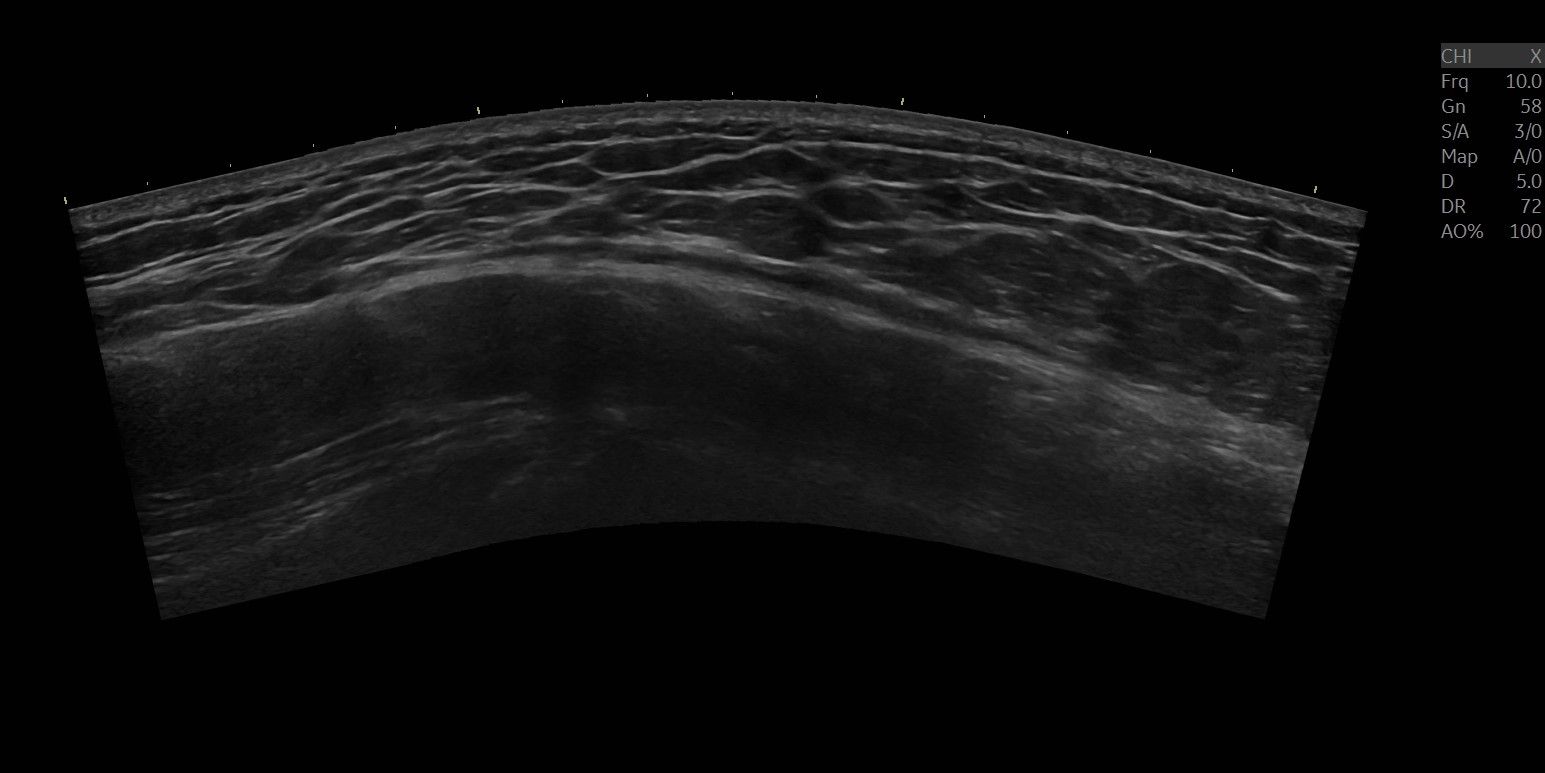

An ultrasound examination shows local bursitis over trochanter.

Below you can see the ultrasound images before, during, and after the treatment.

Bursit longitudinell projektion